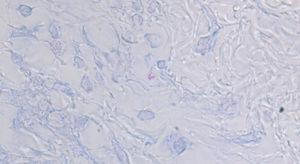

Las exploraciones complementarias realizadas (incluyendo analítica sanguínea con funciones renal, hepática, VSG y PCR y radiografía de tórax) tampoco demostraron ninguna alteración significativa. La biopsia cutánea de una de las placas de la espalda demostró un infiltrado inflamatorio dérmico superficial y profundo con extensión perianexial y perineural, compuesto principalmente por linfocitos y macrófagos, con algunas células epitelioides. Existía daño neural evidente con linfocitos y macrófagos invadiendo algunos nervios (fig. 4). Algunos macrófagos mostraban citoplasmas espumosos. La tinción de Ziehl-Nielsen evidenció BAAR dentro del citoplasma de algunos macrófagos. También se realizó la técnica de inmunofluorescencia con auramina-rodamina y se demostró igualmente la presencia de BAAR.

Fig. 4.--Infiltrado linfocitario dérmico superficial y profundo perianexial y perineural. (Hematoxilina-eosina, x100.)